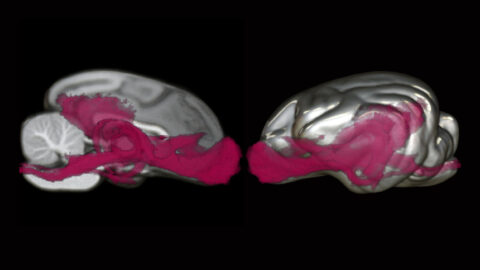

Beauty of the Brain

Each year, we sponsor an image contest where Harvard neuroscientists can share their amazing research images with the world. Below you will find all entries to our contest dating back to 2017. You can filter the contest by year by clicking the relevant heading. We typically solicit new images in the fall semester; join our mailing list to make sure you don’t miss out!